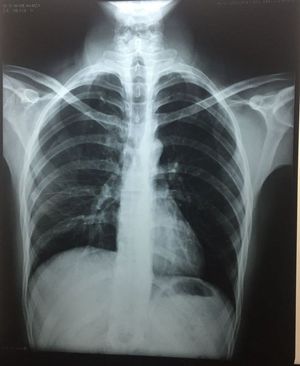

Interpret the X ray

Chest x ray PA view, film slightly rotated to right. Hyperlucency bilateral lung fields left>right.Increased intercoastal spaces.patient may be a smoker. Left lower zone ?Bullae. Chest x ray suggestive of COPD,probably Emphysema.